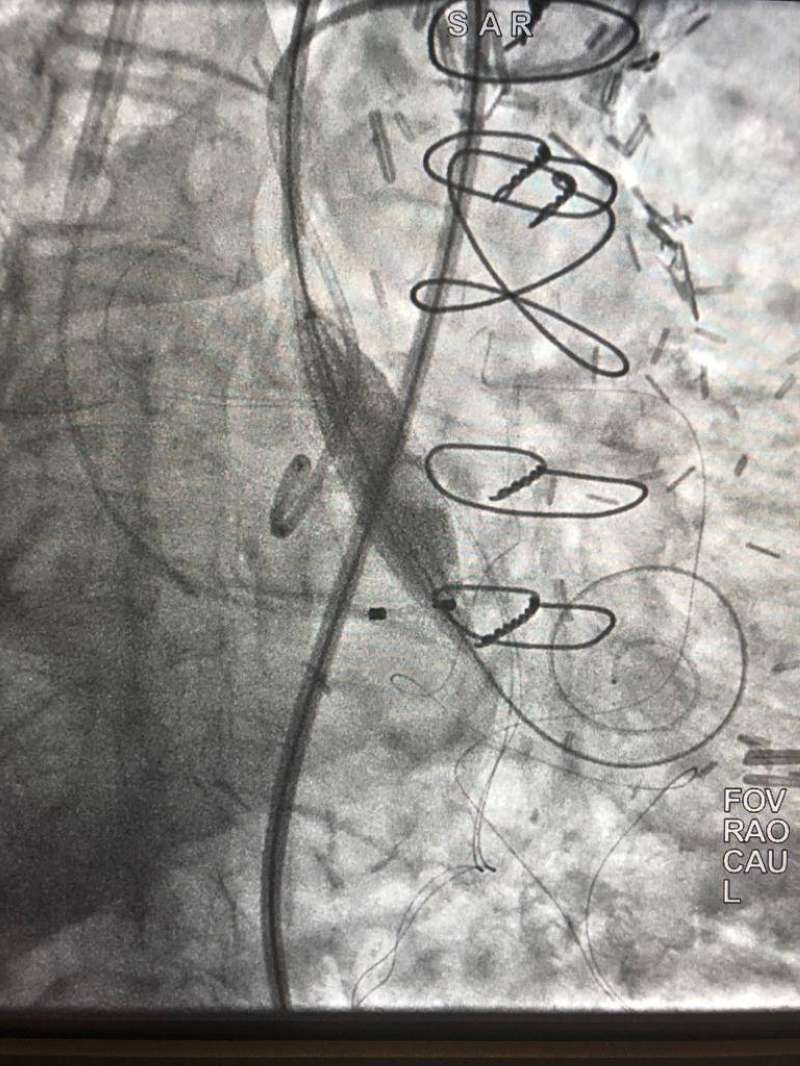

في إنجاز طبي غير مسبوق بدولة الكويت ووسط اجراءات طبية دقيقة نجح فريق طبي في مركز صباح الأحمد للقلب يضم استشاري القلب الدكتور نادر عيسى العسعوسي واختصاصي أول قلب الدكتور أحمد سعيد طه في إجراء عملية تبديل صمام أورطي (TAVI) عن طريق القسطرة لمريض يبلغ من العمر 101 سنة.

ويعتبر ما حدث إنجازاً غير مسبوق ليس من حيث درجة تعقيد العملية أو عمر المريض المتقدم ولكن لإجراء تبديل الصمام بدون استخدام صبغة للحفاظ على وظائف الكلى وهو ما يمثل أيضا اجراء طبيا غير مسبوق، حيث يتم في مثل هذه الحالات استخدام الصبغة لتسهيل إجراء عملية تبديل الصمام التي زاد من درجة صعوبتها و تعقيدها معاناة المريض من ضيق شديد بالصمام الأورطي وفشل عضلة القلب وقصور مزمن بشرايين القلب ووظائف الكلي، وتمدد بالشريان الأبهر في منطقة البطن (abdominal aortic aneurysm with mural thrombus).

وقد استغرقت العملية نحو ساعة وسط إجراءات طبية دقيقة بالنظر لظروف الحالة وتحدياتها بالغة التعقيد؛ حيث بذل فيها الفريق الطبي جهوداً تستحق التقدير وجديرة الثناء، وقد تماثل المريض للشفاء وأصبح بحالة جيدة مستقرة.